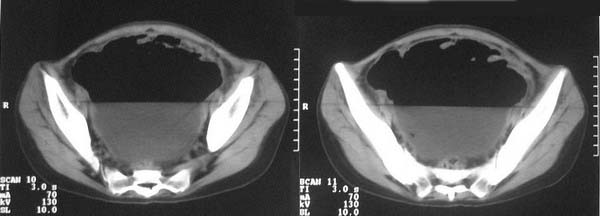

f-18y,腹痛,腹胀,停止排便排气4天,小便正常,四年前阑尾炎手术,病人已手术,明天上传结果。

直肠左侧低密度模糊影,乙状结肠明显扩张,有宽大液平,下腹部肠袢欠规整,内有多发小液平,结合有阑尾炎手术史考虑:直肠周围脓肿,低位肠梗阻,肠粘连。

盆腔巨大脓肿,据术者讲,脓肿大部分壁是有肠管壁形成的,少部分有自己较厚的壁,子宫、附件都泡在脓液里,腹腔肠管广泛粘连,这个病例奇怪的是急性发病,追问不出慢性病史。

结果收到,谢谢楼主,对照结果,回过头看,乙状结肠后壁液性低密度影应该也是脓肿。